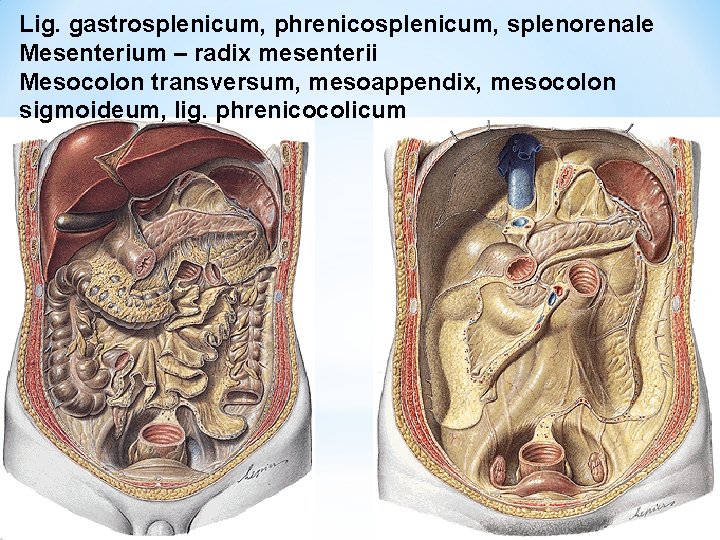

Lig. gastrosplenicum, phrenicosplenicum, splenorenale Mesenterium – radix mesenterii Mesocolon transversum, mesoappendix, mesocolon sigmoideum, lig. phrenicocolicum